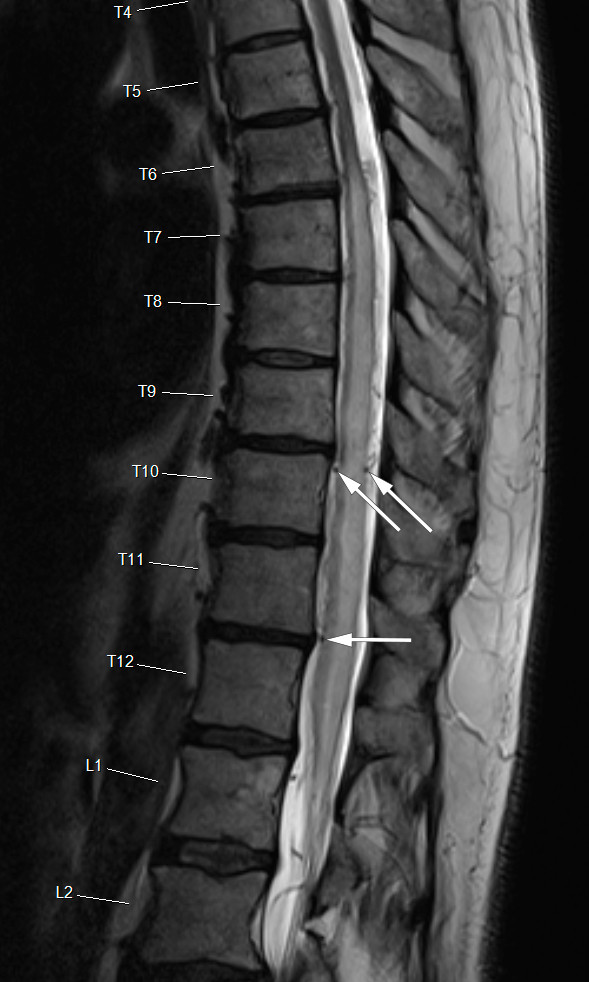

MR caput viste spredte uspesifikke høysignalforandringer periventrikulært, der demyeliniserende forandringer eller kronisk iskemi ikke kunne utelukkes. MR totalcolumna viste uttalt ødem og diffus kontrastoppladning fra nivå TH4/5 og t.o.m. konus, mulig forenlig med demyeliniserende forandringer.

Ved regranskning av MR-bildene ble primærbeskrivelsen opprettholdt. Det var ikke primært mistanke om multippel sklerose og det var ikke påfallende markerte kartegninger. Intramedullær kontrastladning i nedre del av medulla til konus, spesielt anteriort, var diffus og med utseende som myelitt.

Ny MR av ryggen viste uendret intramedullært ødem fra midtre torakalmedulla til konus med vedvarende patologisk kontrastopplading. Det var prominerende karstrukturer omkring medulla (figur 1), og dermed mistanke om arteriovenøs fistel. MR angiografi og spinal digital subtraksjonsangiografi (DSA) viste fistel i nivå L3, forsynt fra venstre L3- lumbalarterie og intradural refluks til perimedullære vener (figur 2). Nevrokirurg utførte stenging av dural arteriovenøs fistel ved hjelp av hemoklips (figur 3a og b).

MR kan vise fortykket medulla med sentralt ødem og eventuelt dilaterte intradurale vener med tydelig signaltap (flow void). Ved MR angio kan man få fremstilt de patologiske venene og eventuelt dural fistel. Digital subtraksjonsangiografi brukes for å påvise og lokalisere den arterielle forsyningen til den durale fistelen. I to nylige studier fant man at ødemutbredelse på MR korrelerte med postoperativt funksjonsnivå (12, 13) på Aminoff-Logue disability (ALD)-skalaen, der funksjon graderes ut ifra gangfunksjon og vannlatingsforstyrrelser (14).